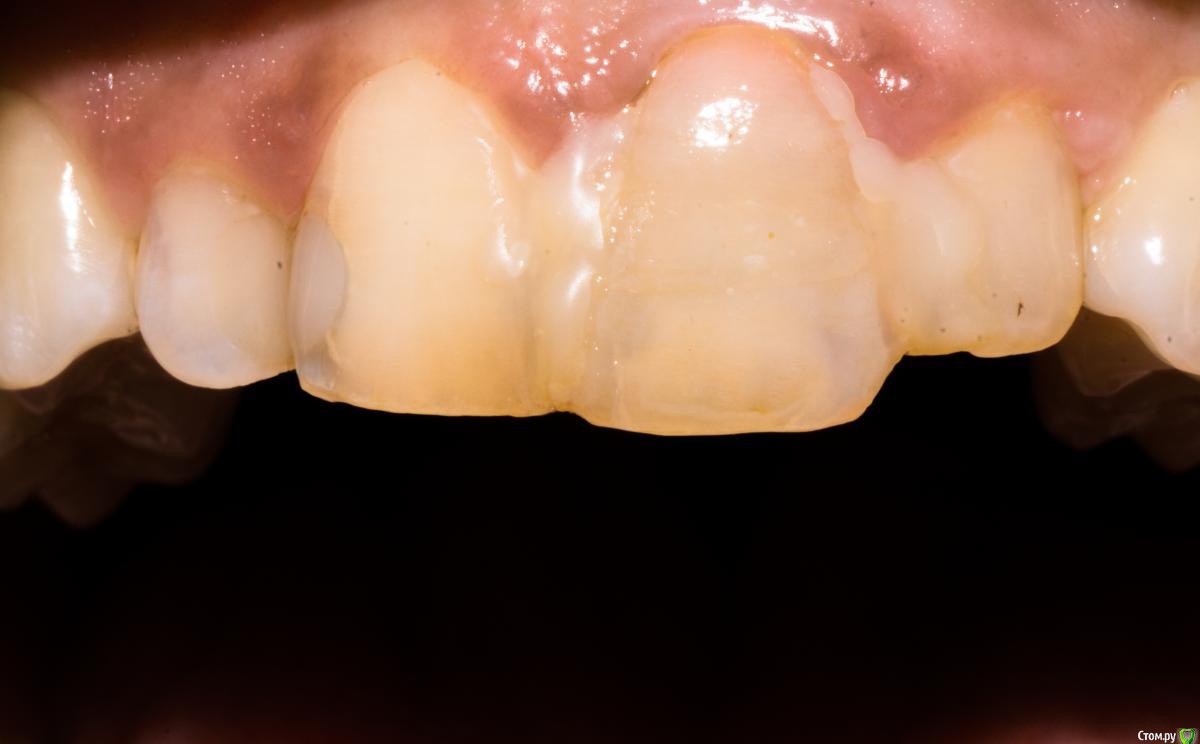

Доктор Добрых Дел Опубликовано 26 ноября, 2016 Поделиться Опубликовано 26 ноября, 2016 Края лунки выглядят как будто в ней граната разорвалась. И согласен с коллегами нужно было ещё заглубить и платформу нёбнее немного. Ссылка на комментарий

togrul Опубликовано 26 ноября, 2016 Автор Поделиться Опубликовано 26 ноября, 2016 (изменено) Края лунки выглядят как будто в ней граната разорвалась. И согласен с коллегами нужно было ещё заглубить и платформу нёбе немного.Спасибо за замечание. При удалении пришлось повозиться. Отлично, надо было заглубить. был графт?Да надо было)Да был Лиопласт. Нужно было Bio oss Изменено 26 ноября, 2016 пользователем togrul Ссылка на комментарий

Nazim_NV86 Опубликовано 27 ноября, 2016 Поделиться Опубликовано 27 ноября, 2016 Я в таких случаях сыплю немного керамики (bego-os) и сст пожирнее. Формик на уровне десны. Никогда не мучаюсь с точным углом имплантата. +-10`. В любом случае будет индивид абатмент. Ссылка на комментарий